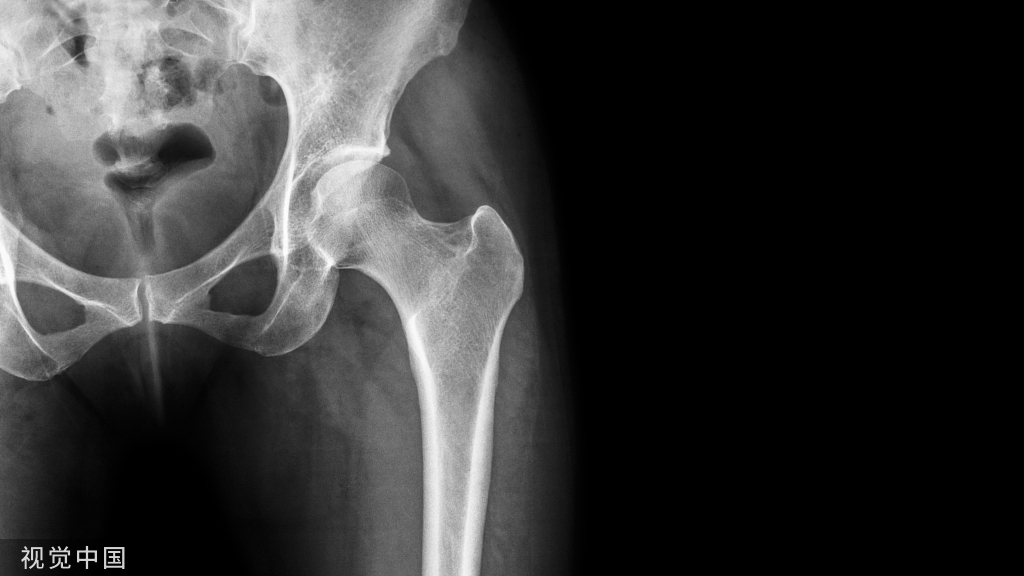

▶▶下肢力线

- 也称作下肢机械轴线。

- 站立前后位股骨头中心与踝关节中心的连线。

- 通过膝关节中心。

- 膝内翻时,位于膝关节中心内侧;外翻时,位于膝关节中心外侧。